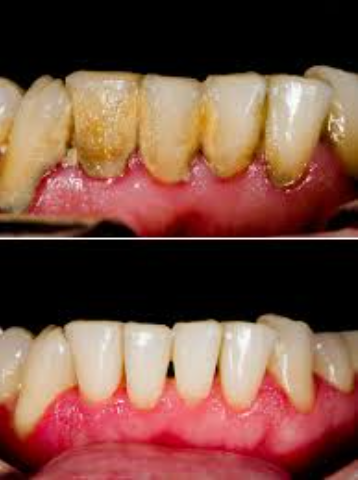

이러한 엄청난 치석을 만났을 때, 가장 먼저 해야하는 것은 '치석제거 = 스케일링' 입니다.

정확히는 눈에 보이는 잇몸 '상방'의 치석을 제거하는 술식입니다.

통상적으로 치과에 방문하셨던 첫 날 진행하게 되며, 평일을 기준으로

기본적인 검사 + 파노라마 엑스레이 촬영 + 스케일링 = 약 3만원 정도 비용이 청구됩니다.

당연히 건강보험 적용이 되기 때문입니다. 대한민국은 건강하게 살기 좋은 나라죠.

이 때 눈에 보이는 딱딱한 치석만 제거하는 것이 아니라, Bioflim 까지 제거해주면 보다 완벽한 치료가 됩니다.

그렇지만 안타깝게도 보통 치석이 저렇게 제거하기 쉬운데만 있지 않습니다.

치아를 뽑아서 보면.. 치석이 자라고 자라 치아 뿌리 표면을 따라 자라들어가거든요..

마치 내성발톱같이 정말 제거하기 힘든 위치로 점점 파고듭니다.

이 치석을 제거하기 위해 '비수술적 잇몸치료'를 시행하게 됩니다.

쉽게 얘기하면, 마취하고 좀 더 깊이 스케일링을 해보는 것입니다.

잇몸과 치아 사이로 기구를 좀 더 밀어넣어서 치석을 깨끗이 제거하면 잇몸이 건강해질테니깐요.

이것이 대부분의 치과에서 (정확히는 치주과 전문의가 아닌 선생님들께서) 시행하는 잇몸치료입니다.

엄청 좋은 치료입니다. 치석이 없어지면 세균이 없어지고 잇몸은 건강한 상태로 돌아오죠.

비수술적 잇몸치료의 비용은 전체 치아를 모두 했다고 가정했을 때, 대략 10만원 안팎 청구됩니다.